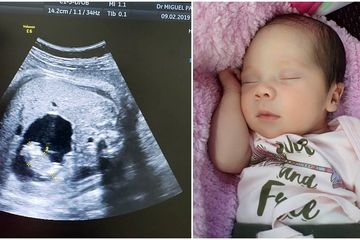

Foto Perkembangan Bayi Kembar Di Dalam Rahim Ibu Hamil Kumparan

Informasi Bayi Kembar Meninggal 1 Dalam Kandungan, karena dalam lebih dari satu hari dan minggu pertama bayi dilahirkan, ada banyak penyesuaian bagi semua orang di lingkungannya, lebih-lebih orang tua. Penyesuaian tersebut sanggup bersifat wujud perawatan, baik secara fisiknya, maupun kebutuhannya Foto perkembangan bayi kembar di dalam rahim ibu hamil kumparan . hamil bayi kembar wanita ini harus bertahan meski satu janin meninggal. salah satu janin kembar marissa nasution meninggal ini penyebabnya orami. hamil anak kembar kemudian lenyap inilah vanishing twin syndrome. kapan jenis kelamin bayi bisa diketahui halaman all kompas . terjadi lagi bayi baru lahir ini mengandung janin kembarannya sendiri sejak dalam kandungan semua halaman grid health. inilah penyebab bayi terlilit tali pusar alodokter Baca juga: Meninggal